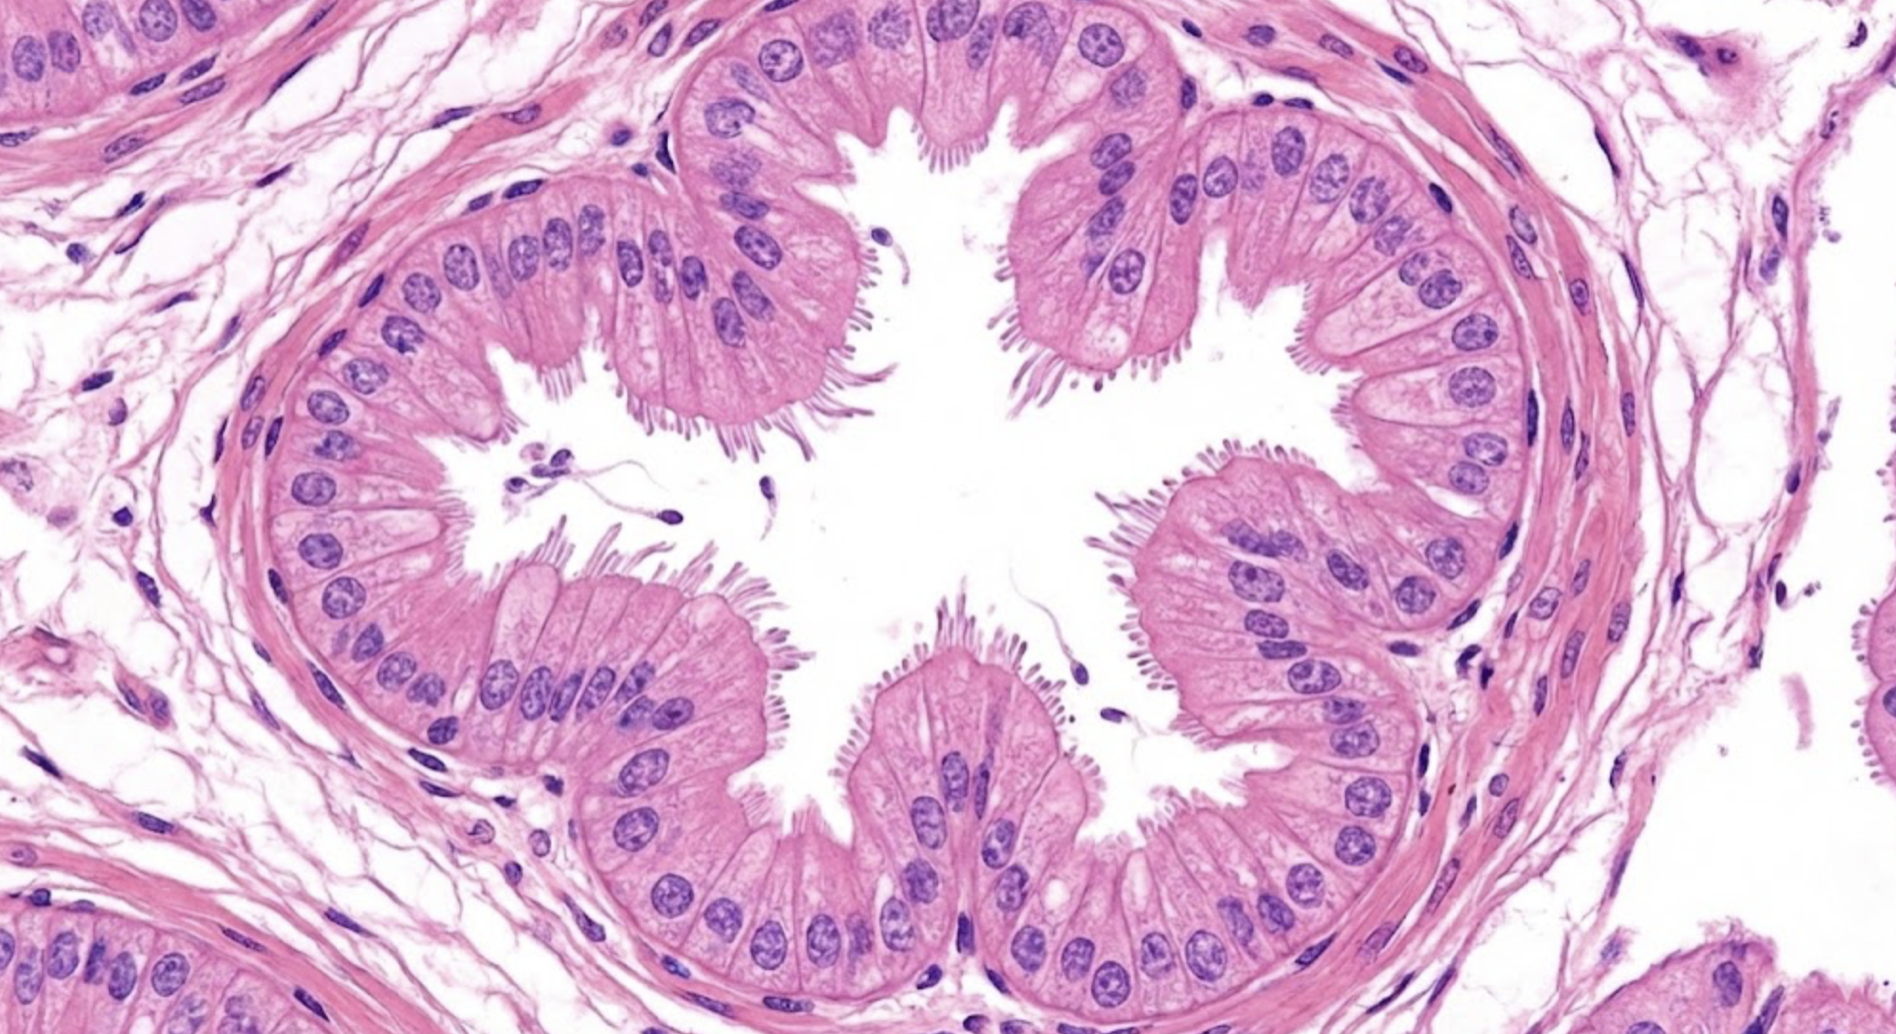

2.30 Welches Element zeigt das rote Symbol in der histologischen Aufnahme (Hämatoxylin-Eosin-Färbung)?

Antwortmöglichkeiten

• (A) Lungenvene

• (B) Alveolarraum

• (C) Arteriolenkapillarwand

• (D) Ductulus efferens

• (E) Alveolärduktus